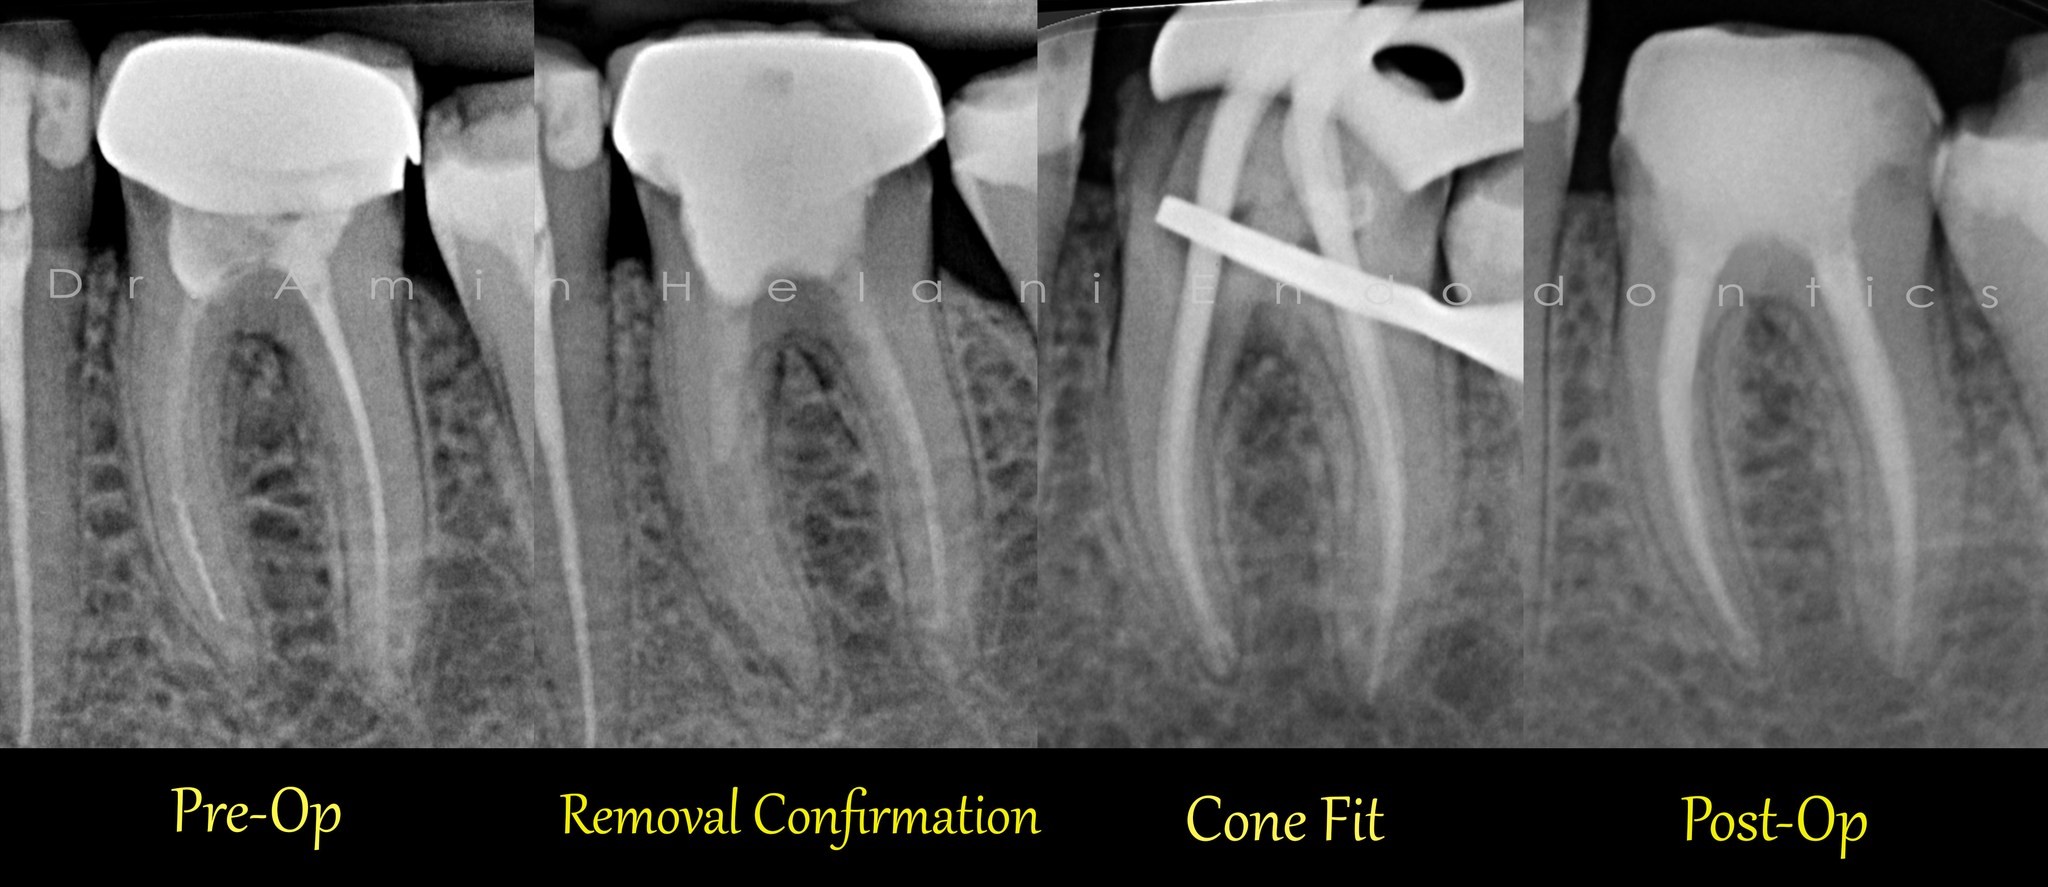

Entfernung von Silberstiften